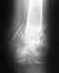

Костная киста большеберцовой кости

Добрый день! 22 августа 2011 г. я была на приеме в вашем институте, где мне поставили диагноз "Костная киста дистального метадиафиза левой большеберцовой кости" и сказали, что в течение полугода вызовут на операцию. Прошло 7 месяцев, но вызова так и не было. Нога по-прежнему беспокоит. Стоит ли мне снова записываться к вам на прием? Номер истории болезни - 268 878. Заранее спасибо.